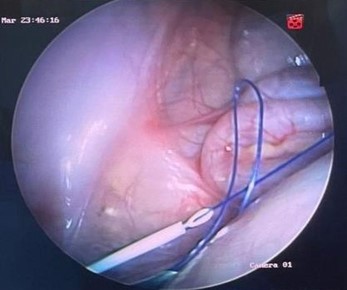

Figura 6. Retiro de aguja y cierre de anillo inguinal interno

Nota: se retira aguja, y a través de la lazada al extraer el hilo en forma de lazada, se rescata el segundo hilo que va a hacer el cierre del anillo inguinal interno.